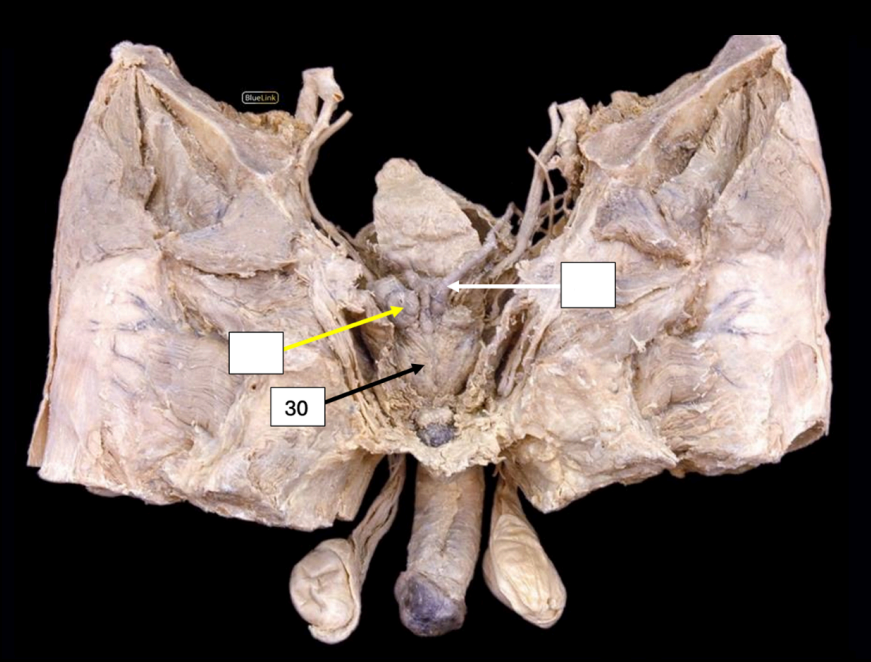

Body of the Uterus

Side Question:

What are the four primary supports of this structure?

Pelvic Diaphragm (Levator ani) - Main Support

*Cardinal Ligament (at the sides)

*Pubocervical Ligament (Anterior)

*Uterosacral Ligament (Posterior)

*Cervical Part

Lymph Drainage: External/Internal Iliac LN (Body and Cervix)

Round Ligament of the Uterus

Artery found in this ligament?

Sampson’s artery (The artery of the round ligament of the uterus)

Lymph Drainage: Superficial Inguinal LN

Broad Ligament of the Uterus

This structure is composed of the following:

Largest that supports the body and fundus of uterus: Mesometrium

Most superior that supports the fallopian tube: Mesosalpinx

Posterior and supports the ovary: Mesovarium